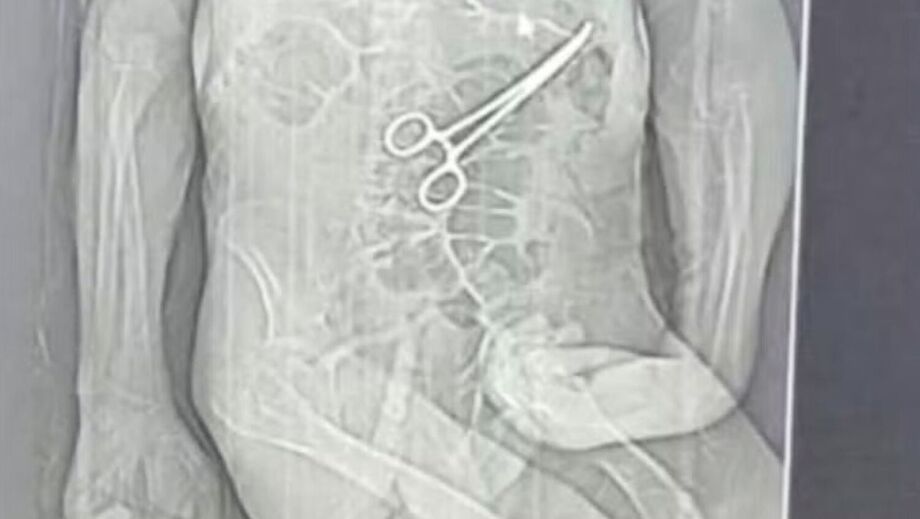

A morte do aposentado Manoel Cardoso de Brito, de 68 anos, na véspera do Natal, levantou suspeitas de erro médico no Hospital Municipal de João Pinheiro, no interior de Minas Gerais, após a família afirmar que uma pinça cirúrgica teria sido esquecida dentro do corpo do paciente durante a primeira cirurgia realizada no início de dezembro.

Logo após a morte, uma rádio local teve acesso a um exame de tomografia que indicaria a presença de um instrumento cirúrgico dentro do corpo do paciente, sustentando a suspeita levantada pela família.

Em nota, a Secretaria Municipal de Saúde de João Pinheiro confirmou que houve a retirada de “um corpo estranho” durante a segunda cirurgia, embora tenha afirmado que o paciente apresentava quadro clínico grave e diversas comorbidades, informando ainda que abriu uma sindicância para apurar o caso e que os protocolos de segurança foram reforçados.

Após a segunda cirurgia, os profissionais de saúde comunicaram aos familiares que haviam retirado pus e um dreno da cavidade interna do paciente, informação que só mais tarde seria associada à retirada de um corpo estranho, conforme confirmado oficialmente pelo hospital.